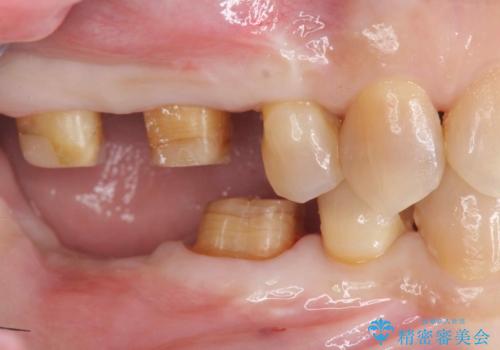

- ぐらぐらする歯や銀歯、なんとなくにおいのする奥歯の治療を求めて来院されました。

X線、歯周組織検査の結果、全体的に奥歯には重度〜中等度の歯周病の問題が見られました。

残すことのできない歯、予後の悪い歯を抜去し、ブリッジイ・ンプラントによる機能回復をおこなっていくと同時に、残すことのできる歯には歯周病治療をしっかりと行い、

将来に渡りしっかりと自分の歯で噛めるような口腔内環境を構築していきます。